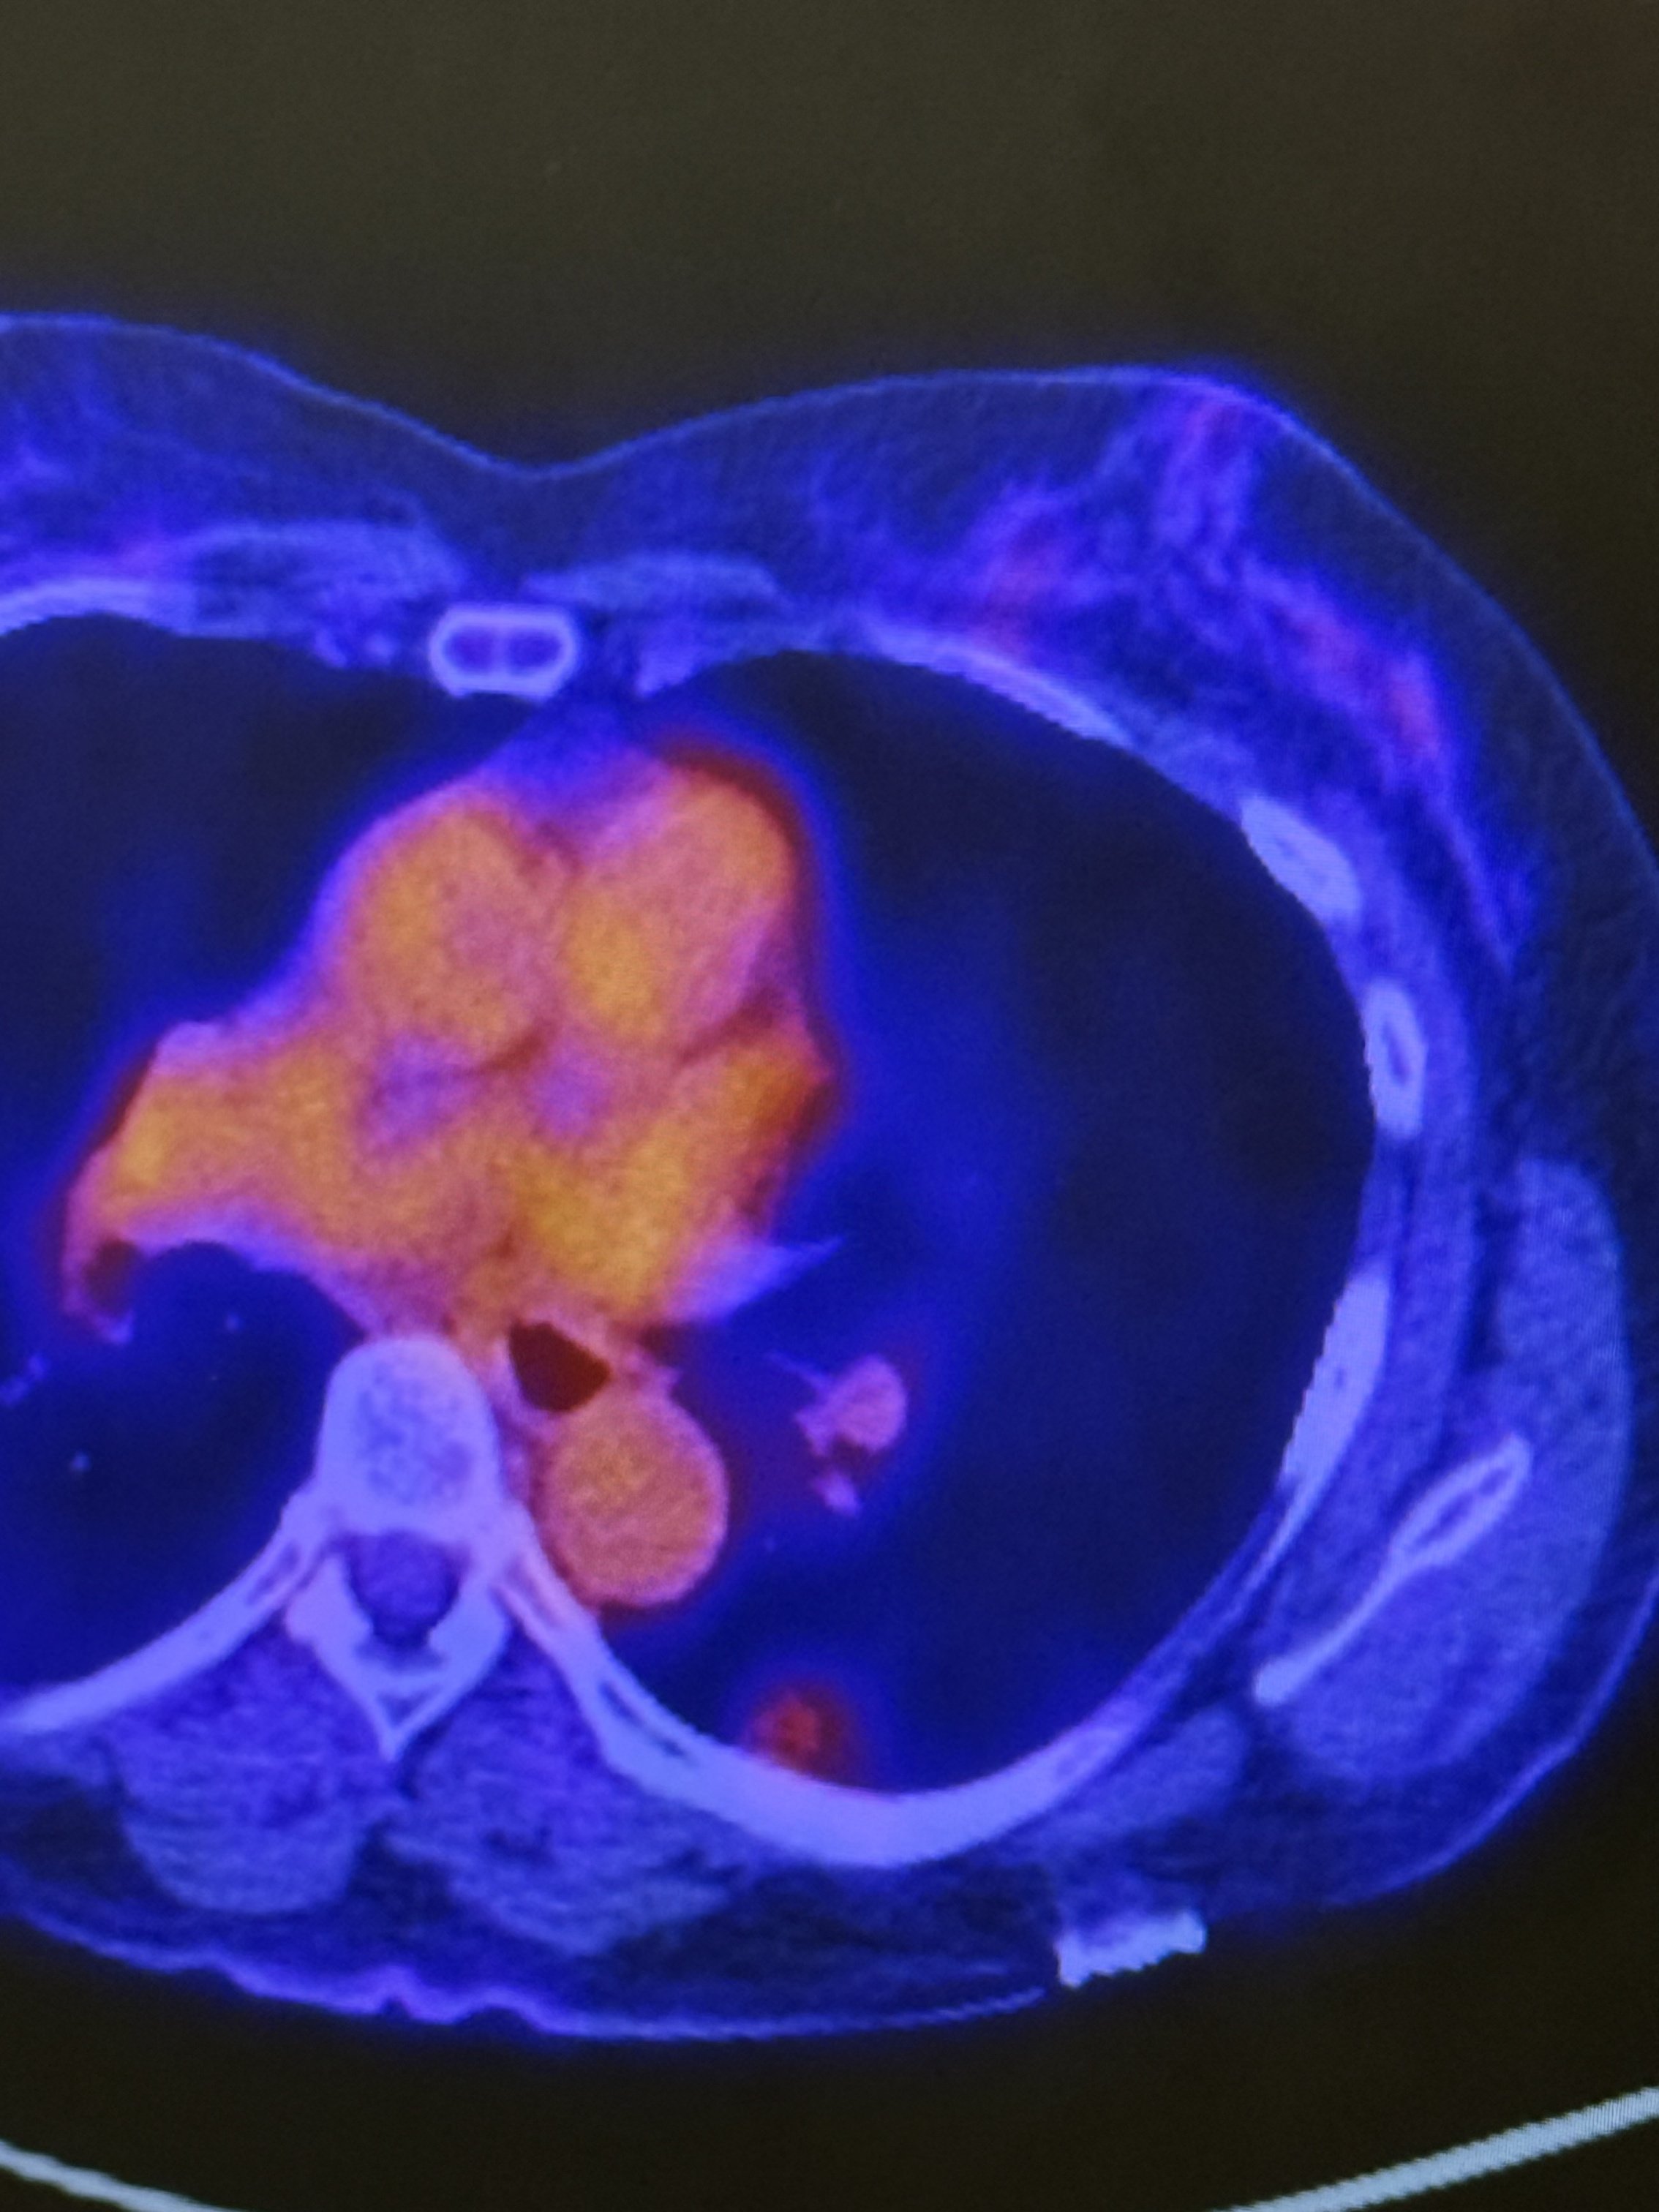

a 12 mm spot was found in my lower left lobe that wasn’t there back in November. CT scan, PET scan, now I have to go back three months which will be April 15 with a new CT scan on March 30.

Not a doctor, but the images you shared look consistent with what you described, a small nodule in the lower left lobe, toward the back, with mild uptake.